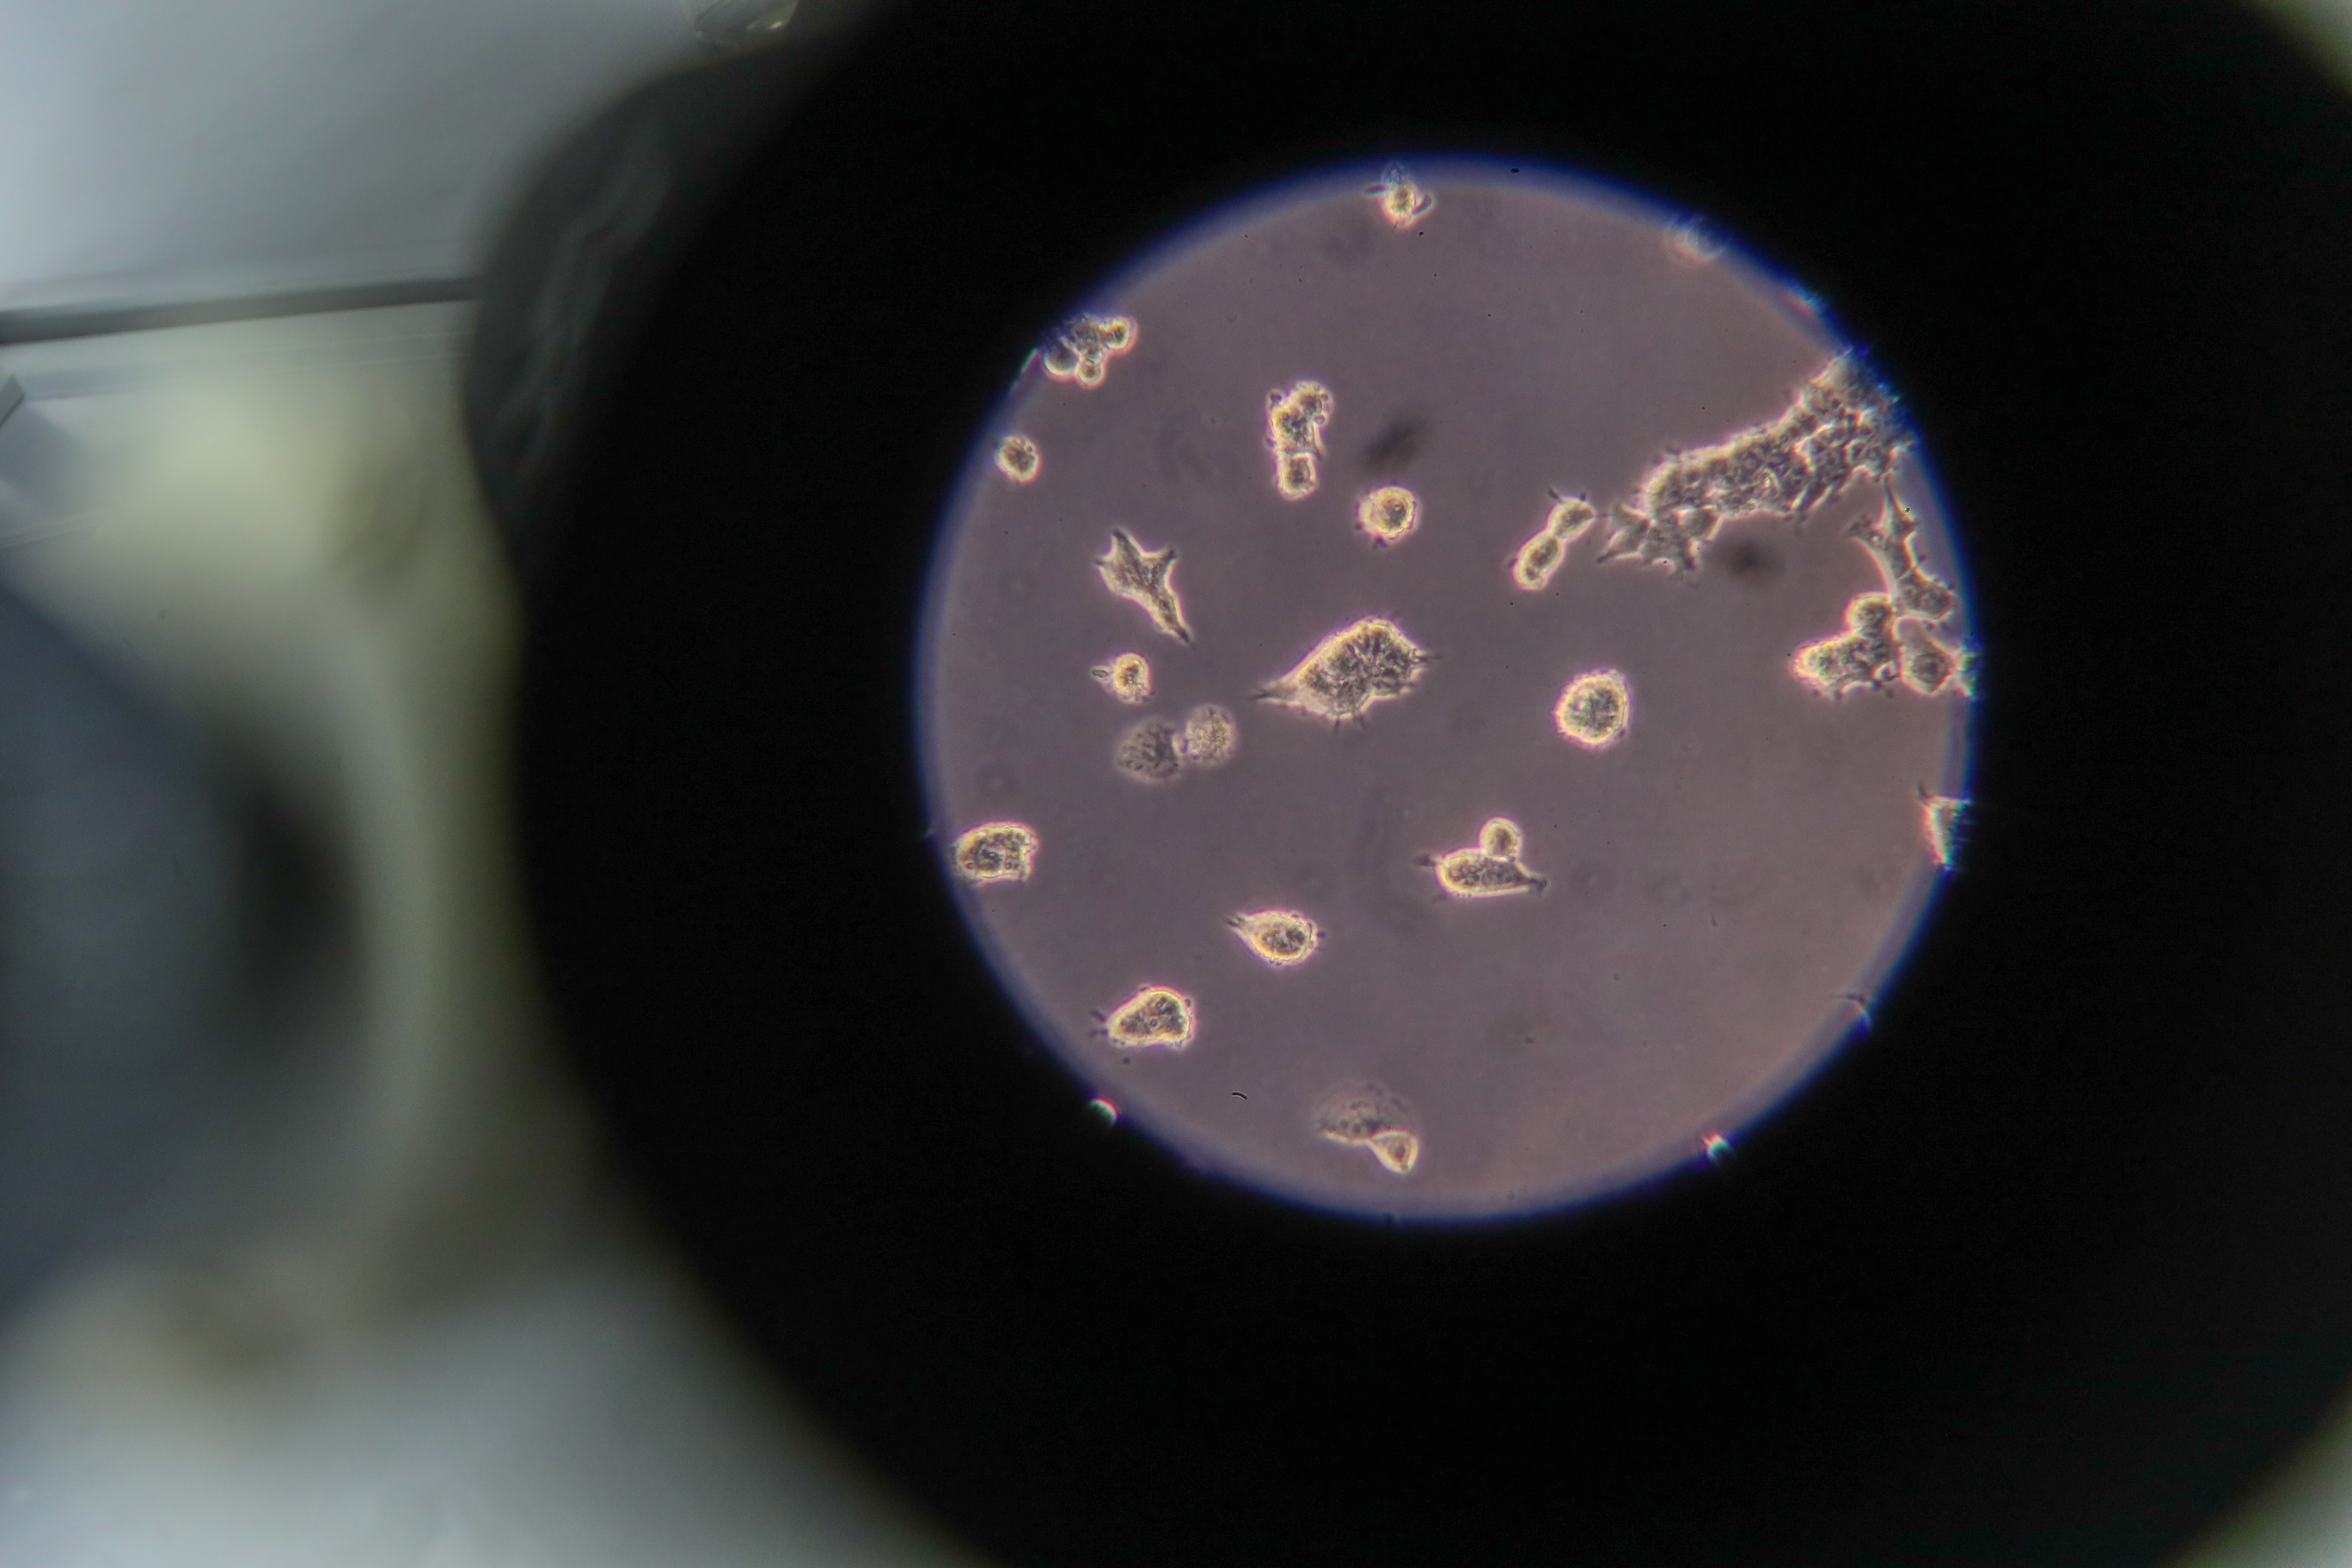

"An analysis of a wide range of clinical and diagnostic parameters on a sampling of over 6,900 patients and those who had COVID-19 with varying degree of severity allowed the specialists of Russia’s Federal Medical Biological Agency to create mathematical models (classifiers) of forecasting the severity and the clinical outcome of COVID-19 based on computerized learning algorithms," the statement said.

It is specified that these algorithms with high precision (about 90%) "confirmed a number of clinical factors that allow to forecast the severity of a course of the disease," for example, such indicators as ferritin, C-reactive protein, ESR, neutrophil-lymphocyte ratio, frequency of breathing, and others.

The possibility of a lethal outcome with the coronavirus infection is increased depending on such factors as age, male gender, the body mass index over 30 as well as on blood sugar levels.

"Within the framework of the study, a genome-wide association study (GWAS) was also conducted on a sampling of over 2,000 COVID-19 patients with a symptomless, mild, moderate, and severe forms of the disease. As a result, genetic variants associated with the severity of COVID-19 were detected," the FMBA statement specified. A statistical analysis of the results of the GWAS also allowed to develop a scale of "polygenic risk of development of a severe form of COVID-19." According to the researchers, this diagnostic algorithm allows to forecast the severity of the disease. Currently it is undergoing the validation stage.

"Thus, the pooled data obtained as a result of the study of the significant clinical and diagnostic parameters and human genetic properties allow to build a unified model of evaluation of the joint contribution of both phenotypic and genetic factors, determining the nature of a course of the COVID-19 disease," the FMBA statement said.